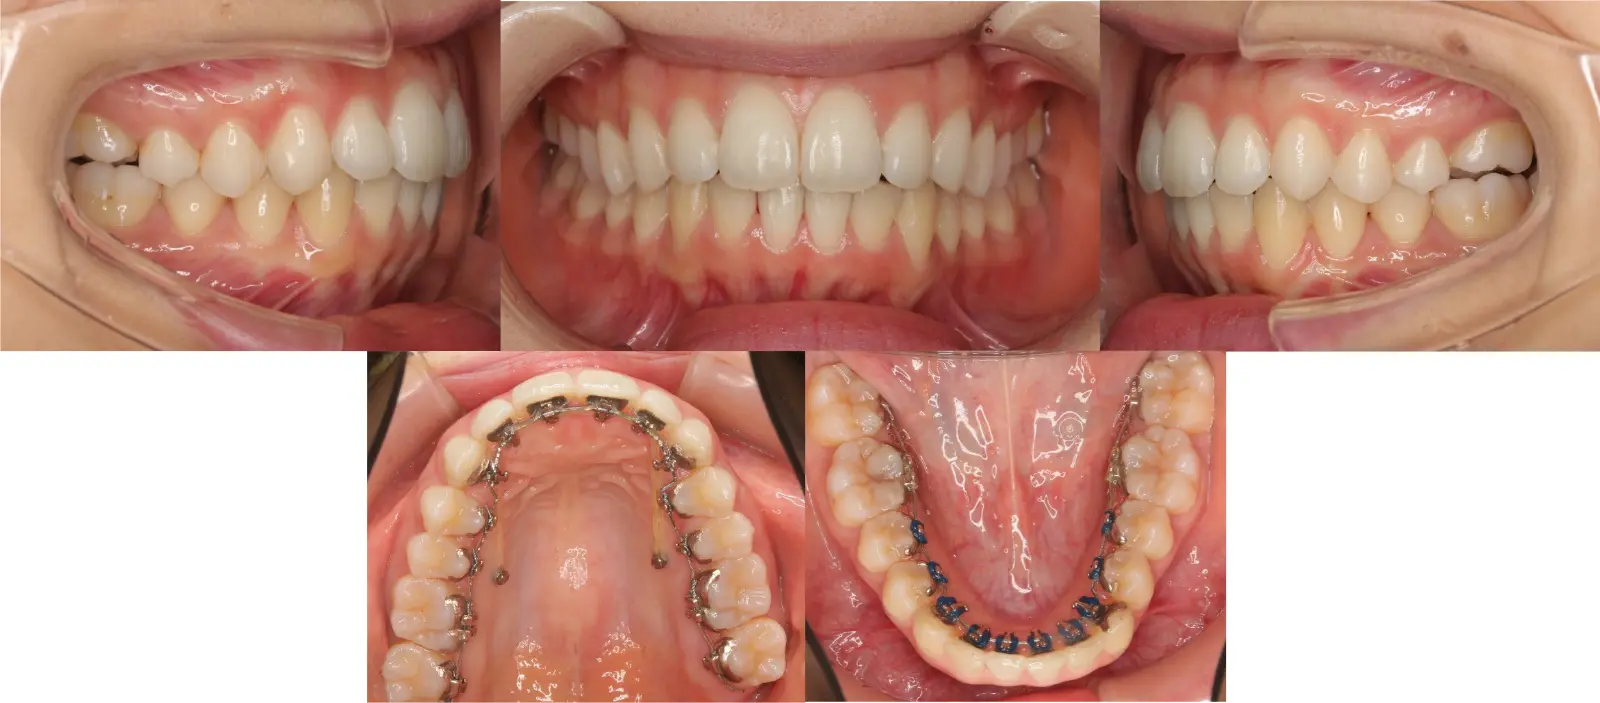

アングルⅠ級 叢生

歯並びがガタガタで気になる

- 年齢

20代

- 治療期間

1年10ヶ月

- 治療回数

21回

- 治療に用いた主な装置

ラビアルのマルチブラケット装置

- 治療費

550,000円(税別)、調整料5,000円(税別)

- 抜歯部位

上下顎第一小臼歯 計4本